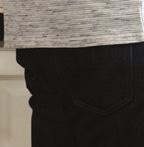

Ingestion de corps étranger par les enfants : épidémiologie, facteurs de risque et prise en charge